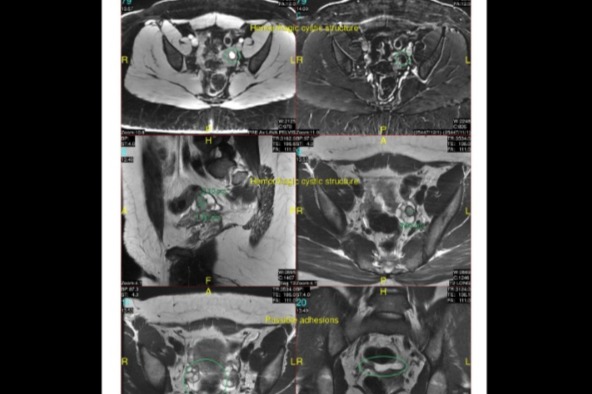

Fast forward to Spring 2021 when I came across the Pelvic Rehabilitation Center. I had been to dozens of doctors so I decided to give them a shot. I showed up to my appointment with Dr. Reuter and by the end of our time together, I was sobbing. He listened to me. Examined me throughly and immediately made me a MRI appointment. When the results returned back, I did in fact have endometriosis and the deep pain I was feeling was my uterus was being pulled back toward my spine by the adhesions. He referred me to my surgeon Dr. Liu who recommended me for laparoscopic surgery. Dr. Liu is an endometriosis expert and she believes this surgery will not only improve my day to day life but also my fertility, when my time comes to have a little rugrat.

(My MRI Results, adhesions and cystic structures shown)